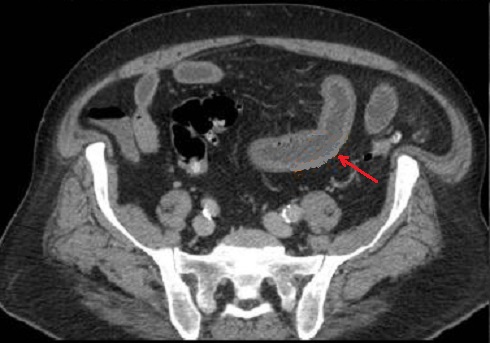

Image d'une thrombus de la

veine cave inferieure ( fleche rouge ) et image de

epaissisement a defaut de rehaussement de la paroi

de l'intestin . Ischemie mesenterique veineux de

l'intestin . Image radiologique TDM en coupe axiale

phase veineuse . |